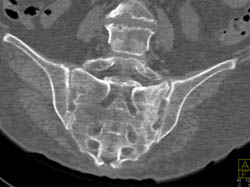

Scaphoid Fracture